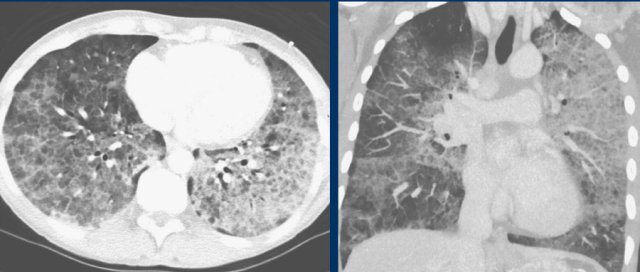

Pneumocystis pneumonia

Pneumocystis pneumonia also causes bilateral ground-glass and in later stages consolidations with or without crazy paving.

However, this frequently occurs in a more central distribution than in COVID-19, and only in immunocompromised patients.

PCP is furthermore associated with pulmonary cysts and spontaneous pneumothoraces, although pneumothoraces and bullae also present in a small minority of hospitalized COVID-19 patients.

Adult respiratory distress syndrome

Diffuse alveolar damage can also show peripheral ground-glass, consolidations and crazy paving, which can be similar to the alveolar damage in patients with COVID-19 (left), but also more gravity dependent reflecting permeability edema (right).

ARDS can only occur in the appropriate setting, such as in a postoperative situation or in case of prolonged mechanical ventilation.

However, ARDS can concomitantly occur with COVID-19 in ICU patients.